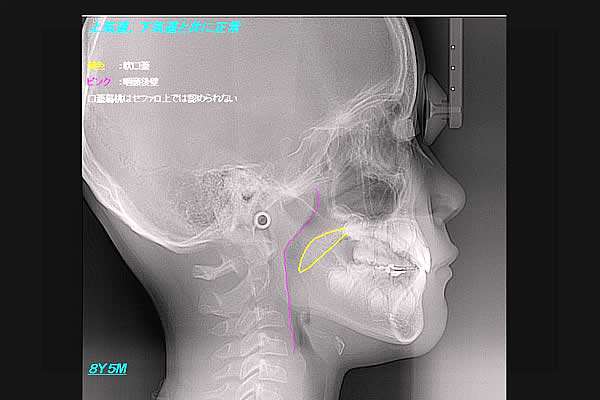

さて扁桃腺が腫れている子ども達の、X線側貌セファロ写真を撮影してみた。まず、鼻呼吸をしている男児。

(図4)

扁桃腺が腫れている子ども達のX線側貌セファロ写真

ピンクは咽頭後壁。黄色は軟口蓋である。軟口蓋と咽頭後壁の間にが、気道が見える。これが正常像。次に、鼻閉のため口呼吸をしている男児。